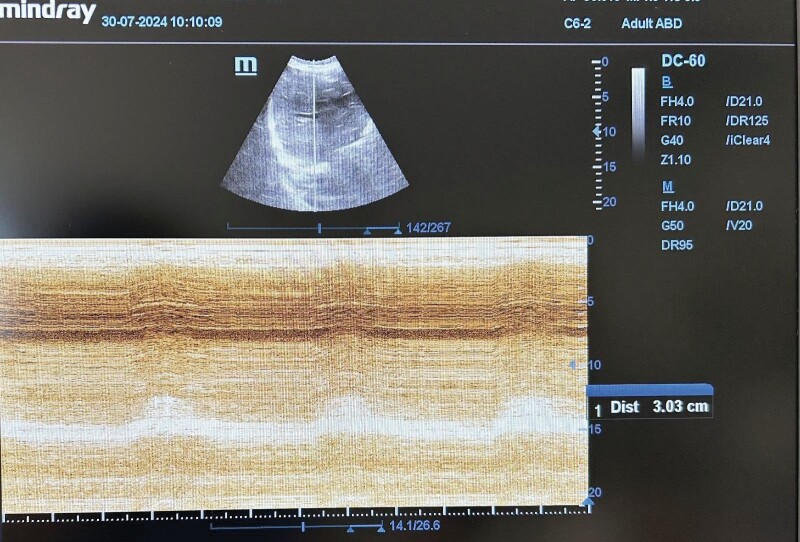

Materials and methods: The lung parenchyma and diaphragm of 50 patients were investigated using ultrasound (USG) on day 1, 5, and 10 of MV therapy.

Result: Mean age of the patients was 64.90 ± 15.96 years. Mean MV duration was 90.18 ± 21.09 days. Mean thickening fraction (TFdi) on day 1, 5, and 10 was 40.77 ± 15.42, 39.85 ± 16.85, and 43.57 ± 19.10, respectively. Mean diaphragm amplitude on day 1, 5, and 10 was 1.70 ± 0.74, 1.76 ± 0.74, and 1.70 ± 0.71, respectively. Mean diaphragmatic thickness at the end of expiration (Tde) on day 1, 5, and 10 was 0.18 ± 0.08, 0.17 ± 0.06, and 0.16 ± 0.05, respectively. There was no significant change between measurement days by TFdi, diaphragmatic amplitude (DA), and Tde values. On admission, TFdi was less than 20% in 8% of the patients, DA was less than 1 cm in 12%, and Tfde was less than 0.2 cm in 52%. There was no significant difference by the TFdi, DA and lung ultrasonography (LUS) scores of the non-surviving and surviving patients. An analysis of imaging results and LUS scores indicated that LUS values were measured higher in patients with infiltration on chest radiography. In addition, LUS scores significantly decreased from day 1 to day 5 and day 10, and from day 5 to day 10.